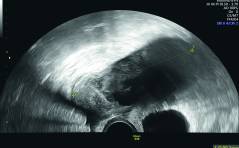

Sonoquiz - Wo liegt die Auffälligkeit?

Dieses mal ist es leicht, oder? Schwieriger ist es, dies der Frau zu erklären, ohne dass sie in eine Krise fällt. Aufnahme in der 29. Woche. Kind normal gewachsen. Um was handelt es sich? PDF Dokument

Sonoquiz Auflösung - Vorzeitiger Verschluss der Sutura frontalis mit Trigonocephalie

Craniosynostosen sind definiert als vorzeitiger Verschluss von Schädelnähten. Kinder mit solchen Synosto-sen stellen eine heterogene Gruppe dar, oft assoziiert mit klaren klinischen, genetischen und molekularen Charakteristika. Craniosynostosen wurden ... PDF Dokument